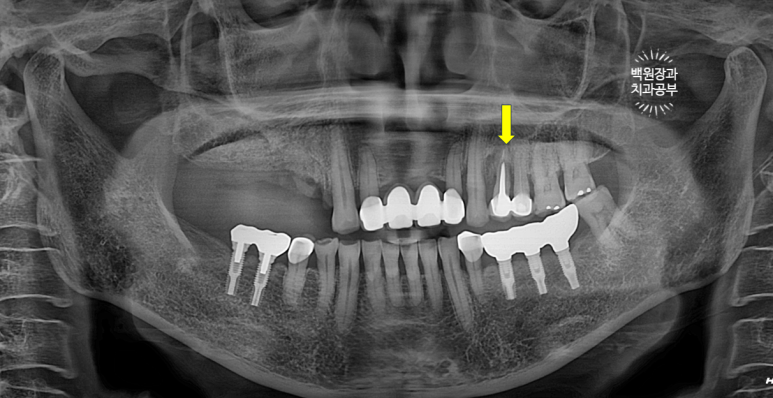

임플란트 1차수술 후 3개월을 더 기다려 임플란트 2차수술을 합니다.

정확히는 3개월 반 정도 기다려서 임플란트 2차수술을 해드렸습니다.

아무리 날고 기는 회사의 임플란트 뼈이식재라도... 사용되고나서 내 뼈처럼 단단해지려면 4개월은 필요합니다.

4개월을 기다려도 조직학적 소견을 살펴보면 정작 내 뼈는 많지 않죠.....

그래서 만들어진 그 잇몸뼈에 임플란트를 심고나서 또 넉넉히 3-4달 기다려야 합니다.

이렇게 잇몸뼈 안에 있는 임플란트에 뚜껑을 끼우면 그게 임플란트 2차수술입니다.

그래서 저는 임플란트 2차수술을 하며 근단변위판막술 (apically positioned flap)을 함께 해주면서 전정성형술 (vestibular deepening)을 함께 해주어 임플란트 완성 후에 관리가 용이한 환경을 조성해 드린 것입니다!

수술 전의 사진과 비교해서 생각보다 임플란트가 원래 자리와 비슷한 레벨에 위치해 있음을 확인할 수 있습니다.

이게 모두 임플란트 제거와 동시에 시행했던 덴티움 뼈이식재를 이용한 치조골 이식술 덕분입니다.

수술 전에 비해 약 1-2mm 정도 임플란트 크라운이 길어진 느낌이네요.